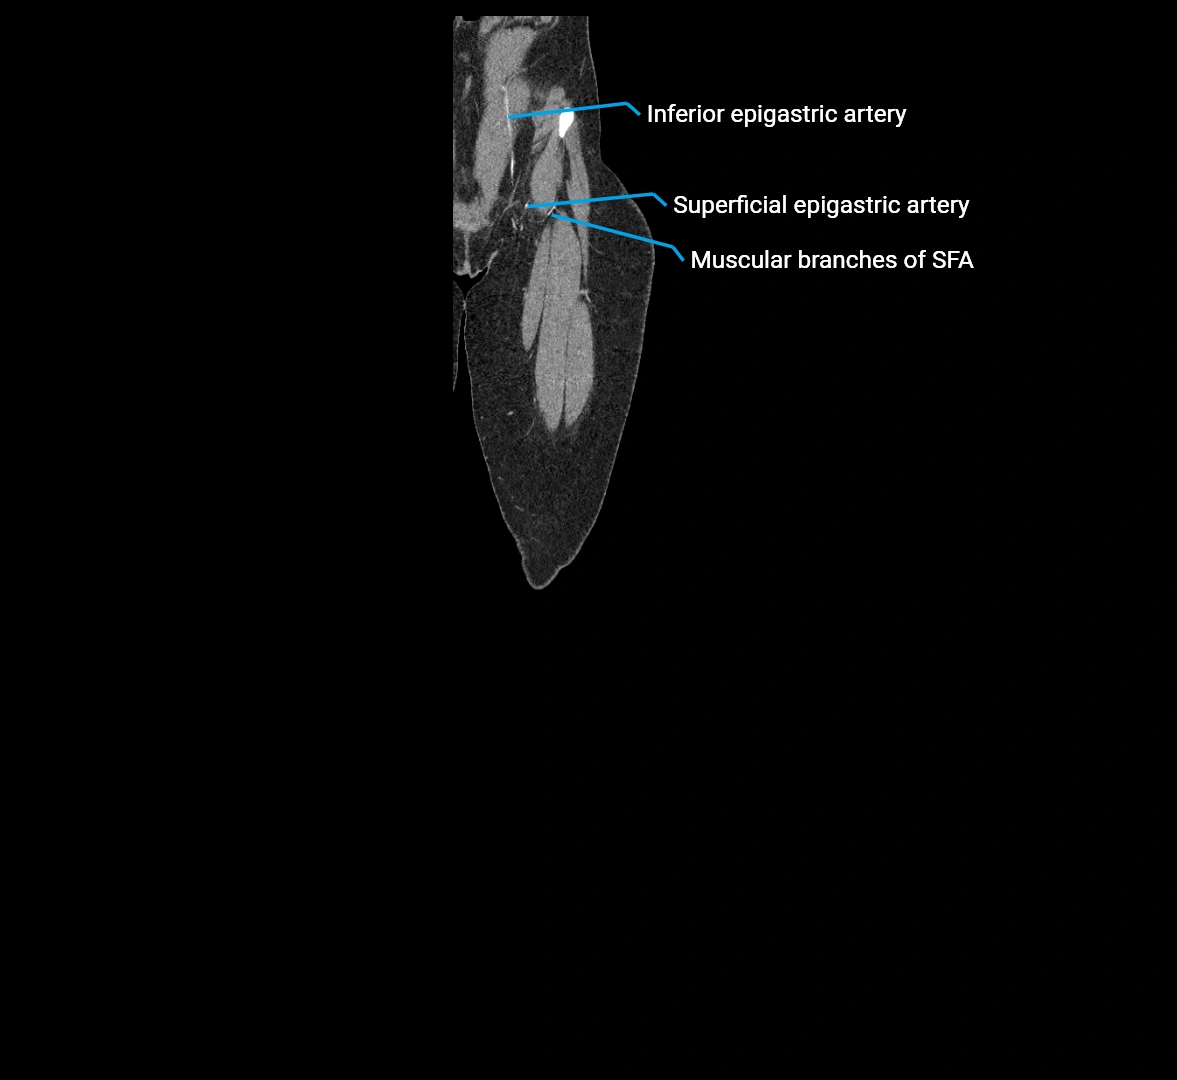

MRI images

image